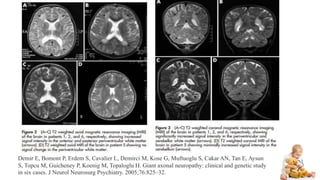

5. MRI showing cerebellar and white matter abnormalities :

High signals on T2 sequences in the anterior and posterior

periventricular regions as well as the cerebellar white matter

Demir E, Bomont P, Erdem S, Cavalier L, Demirci M, Kose G, Muftuoglu S, Cakar AN, Tan E, Aysun

S, Topcu M, Guicheney P, Koenig M, Topaloglu H. Giant axonal neuropathy: clinical and genetic study

in six cases. J Neurol Neurosurg Psychiatry. 2005;76:825–32.